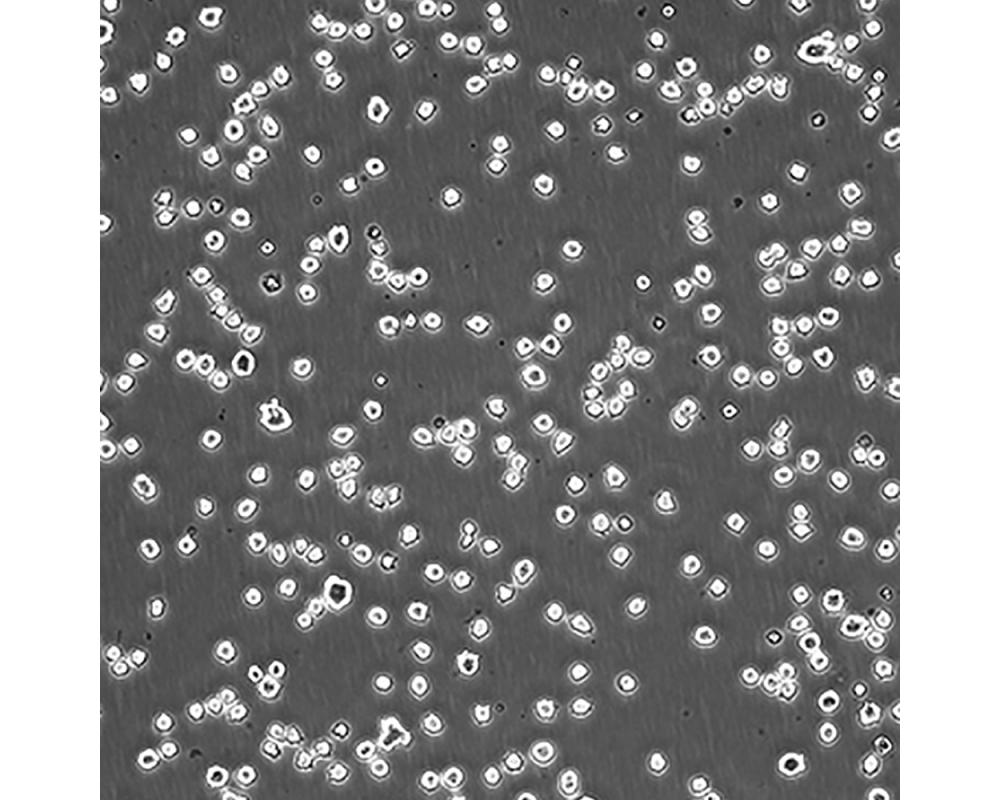

產品名稱 DB

中文名稱 人彌漫性大B細胞淋巴瘤細胞

組織來源 彌漫性大B細胞淋巴瘤;男性

生長特性 懸浮

培養基 DMEM90%;FBS10%;1%雙抗。

傳代方法 Maintain cultures at a cell concentraion between between 1 X 10(5) and 1 X 10(6) viable cells/ml.

培養條件 Atmosphere: Air, 95%; CO2, 5%。Temperature: 37℃